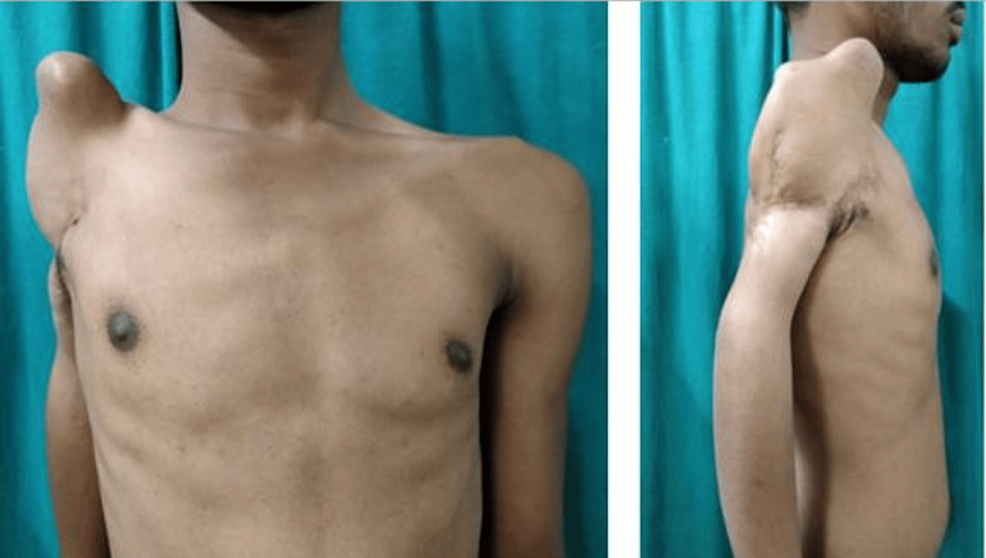

Shoulder Dislocation

Joint instability due to trauma or sports injury.